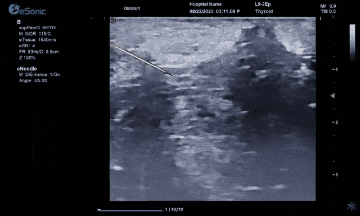

百乐博平台医疗(ESI)表示,其最新的人工智能功能可以帮助到医疗机构的工作效率,功能包括,实时、动态、快速自动识别病灶,良恶性病灶概率预测,甲状腺结节和乳腺的二维灰阶动态自动实时检测需求,提供多个结节动态检测轮廓框。实时获取多幅具备临床特征(大小、属性等)的结节切面,同时提供当前切面所示结节的结节大小、属性特征、TI-RADS 分级。

对于甲状腺结节相关的自动检测功能,甲状腺结节病灶检出率≥95%,良恶性分类灵敏度≥90%、良恶性分类特异度≥85%。